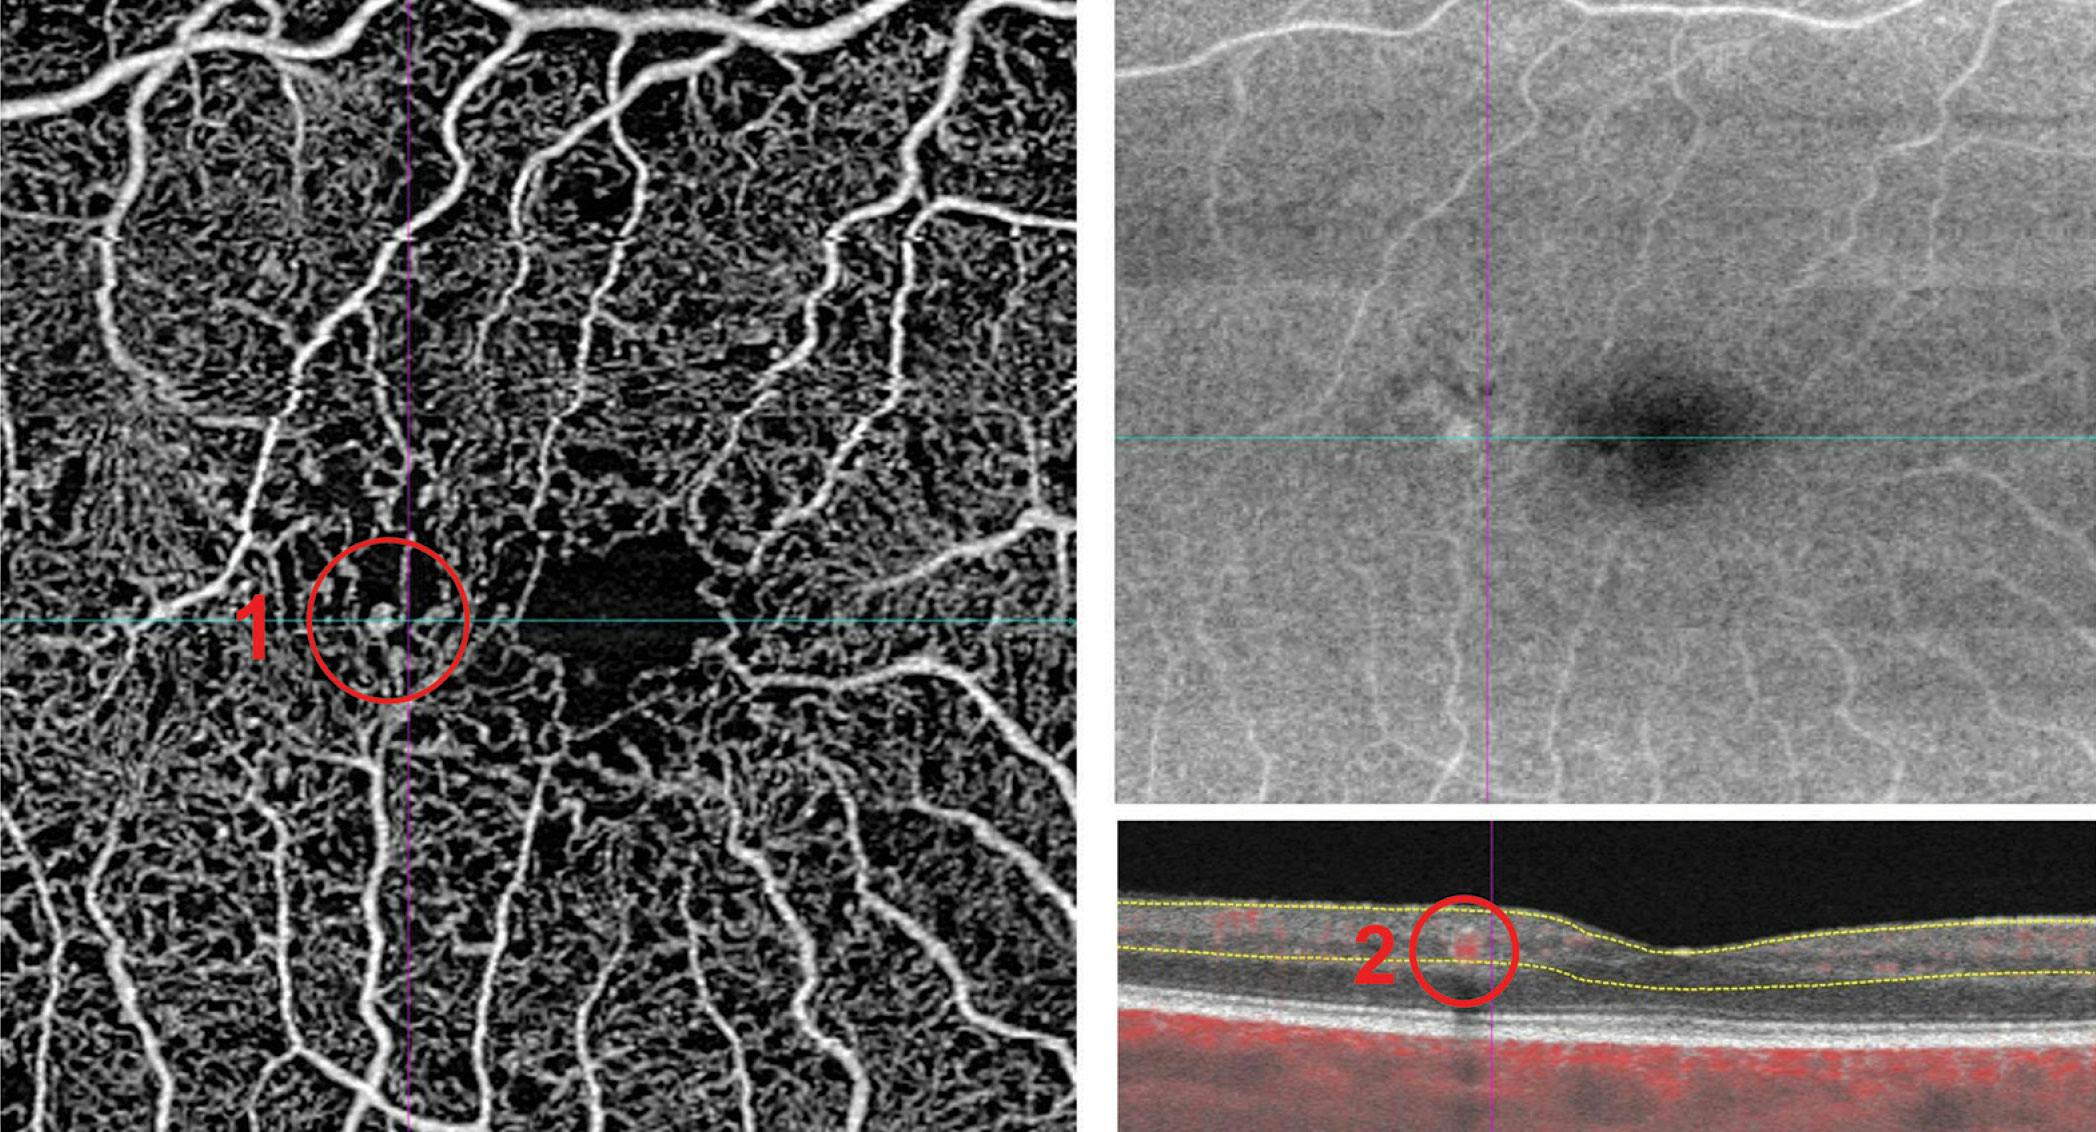

After several rounds of refinement, the final framework was distributed via a survey to IntRIS members. They were asked to apply the framework to describe a series of provided OCTA examples (Figure 1).

<p>Figure 1. This is the first OCTA image that experts were asked to describe using the proposed nomenclature framework. They were also asked how comfortable they felt using the proposed nomenclature. Descriptions of the marked area (red 1 and 2) include: “The OCTA images reveal a 6 mm x 6 mm macular SCP en face slab with a focal increase in OCTA signal, indicative of a microaneurysm”; “The OCTA B-scan shows an abnormal OCTA signal extension intraretinally, likely at the boundary between the inner nuclear layer and the outer plexiform layer, consistent with a microaneurysm originating from vascular abnormalities”; and “Increased OCTA signal consistent with a microaneurysm.”</p>

Figure 1. This is the first OCTA image that experts were asked to describe using the proposed nomenclature framework. They were also asked how comfortable they felt using the proposed nomenclature. Descriptions of the marked area (red 1 and 2) include: “The OCTA images reveal a 6 mm x 6 mm macular SCP en face slab with a focal increase in OCTA signal, indicative of a microaneurysm”; “The OCTA B-scan shows an abnormal OCTA signal extension intraretinally, likely at the boundary between the inner nuclear layer and the outer plexiform layer, consistent with a microaneurysm originating from vascular abnormalities”; and “Increased OCTA signal consistent with a microaneurysm.”